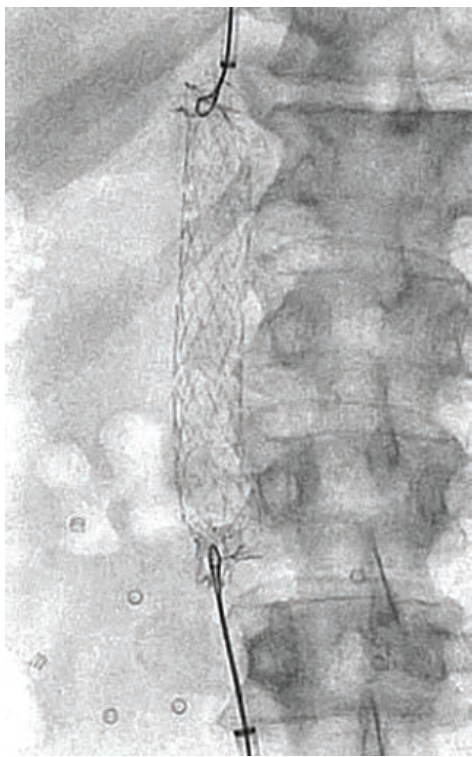

The cath lab team began by deploying the cerebral protection device filters in the right brachiocephalic and left common carotid arteries via a 6 French (F) radial sheath. Access to the right common femoral artery was obtained with ultrasound and micropuncture. Following a pre-closure device, a 12F sheath was inserted. The LVAD speed was 0.8 L/min, and the patient’s mean arterial pressure (MAP) was 75 mmHg with pressors. The outflow graft was cannulated with a Stiff Glidewire and a 5F GlideCath (both Terumo Interventional Systems). The shorter sheath was exchanged for a Shuttle sheath (Cook Medical), and an injection was performed through the GlideCath. This image showed a clear obstruction at the bend relief space, causing the kink and low flows.

An 11 mm x 16 mm covered stent was placed, followed by an .035-inch 10 mm x 40 mm balloon, but the kink remained. A 12 mm x 40 mm percutaneous transluminal angioplasty (PTA) balloon was inserted and the kink gave. However, the flows did not improve and, in fact, temporarily dropped.

The precipitous drop in flow was caused by the pannus shifting toward the proximal outflow graft near the pump housing. The team quickly deployed an 11 mm x 16 mm stent to support the proximal graft, followed by a 12 mm x 40 mm PTA balloon. The patient’s LVAD flow improved to a remarkable 4.5 L/min.